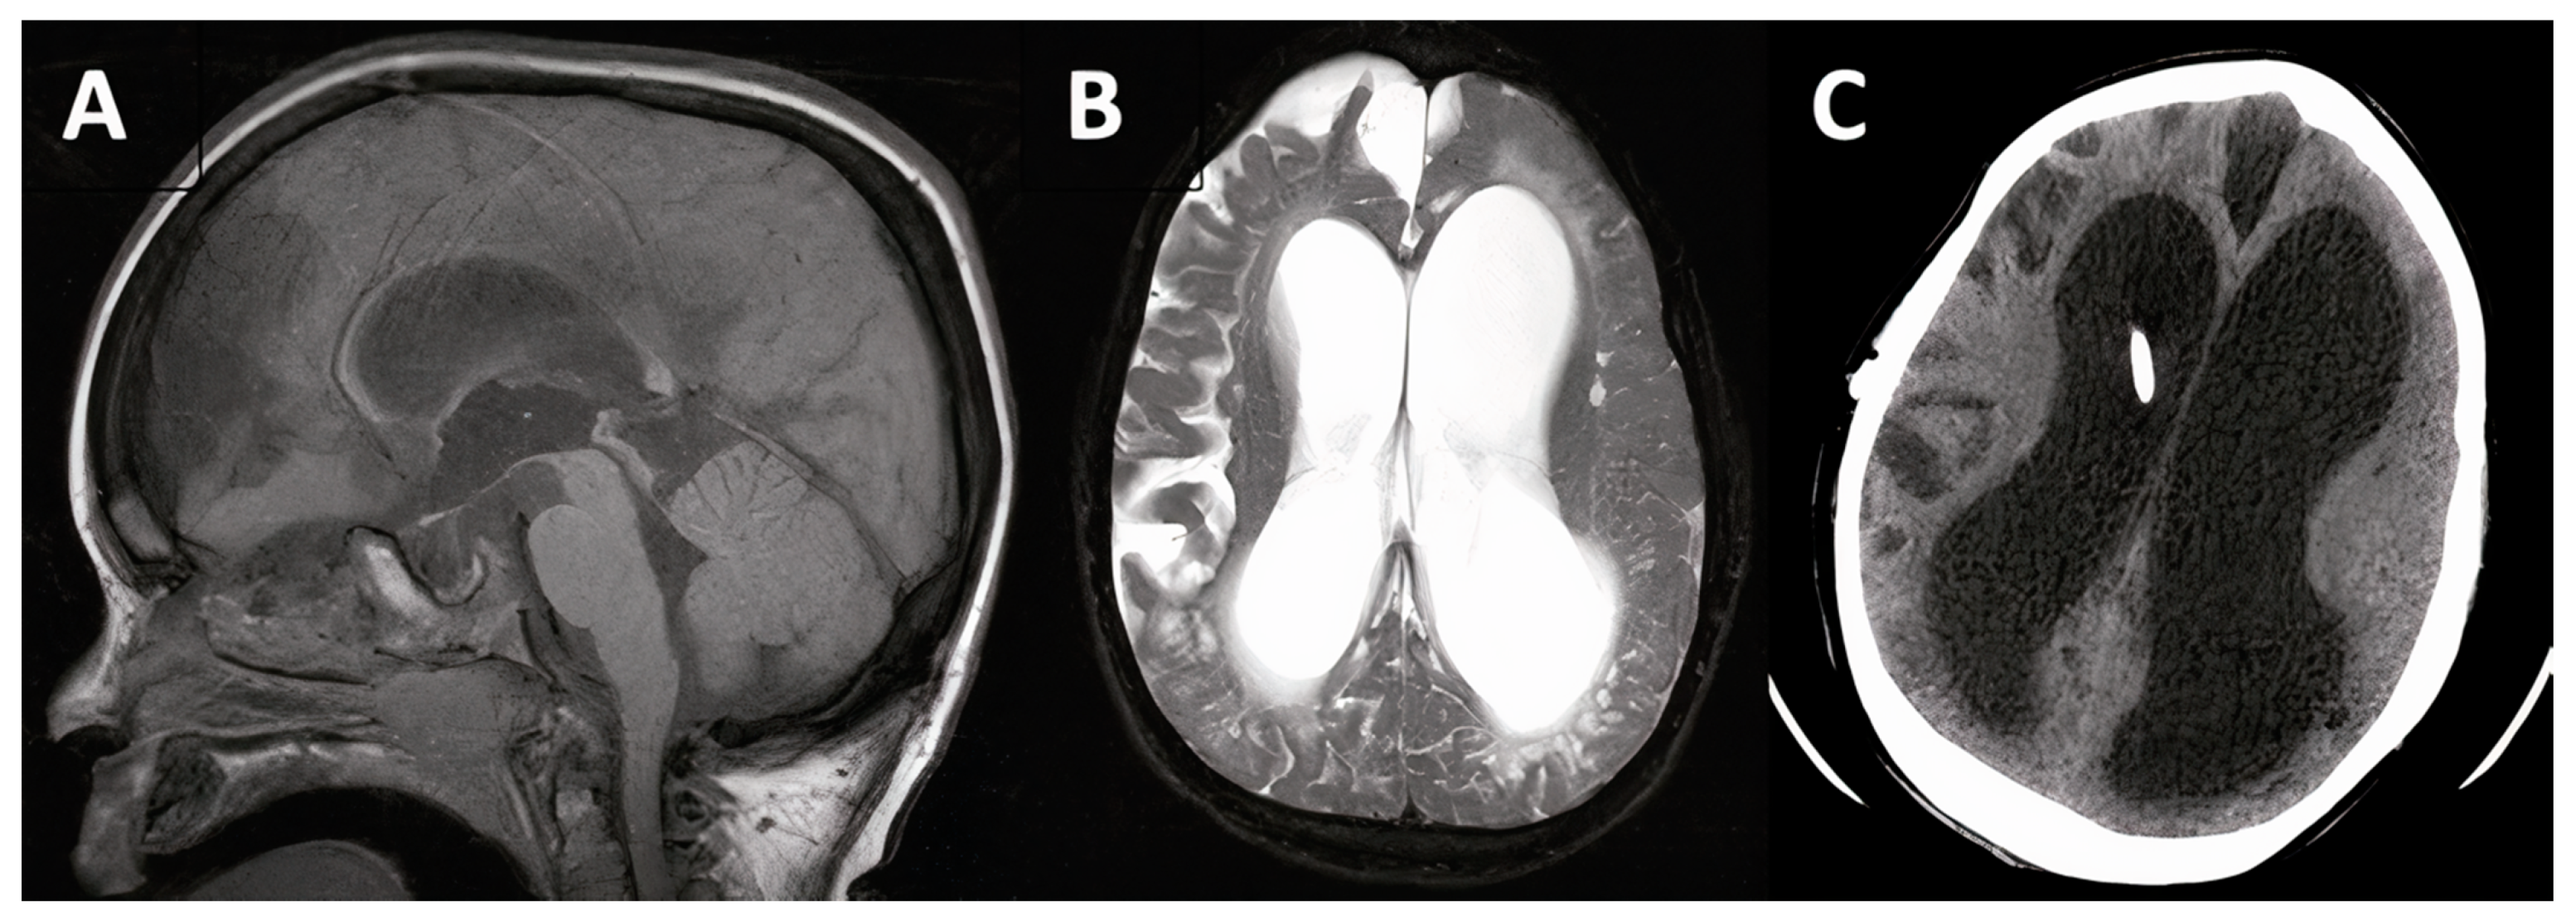

3.1.3. Case #4. Congenital Hydrocephalus with Prematurity

| 4 | 18 m, F |

|